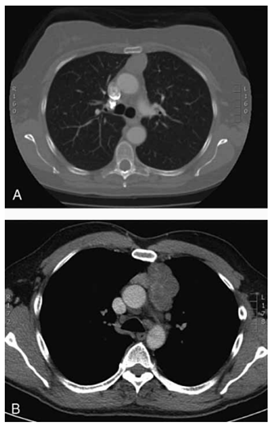

Mulher, 42 anos, queixa-se de fadiga progressiva com diplopia ao final do dia há 6 meses. Exame neurológico sugere fraqueza fatigável; sorologia para anticorpo anti- -receptor de acetilcolina é positiva. Radiografia de tórax mostra alargamento do mediastino anterior. A tomografia computadorizada de tórax com contraste mostra uma massa encapsulada no mediastino anterior, sem invasão evidente de estruturas adjacentes (imagem demonstrada a seguir). Não há adenomegalias mediastinais perceptíveis.

Enunciado 4925949-1

(Townsend Jr., C. M.; Beauchamp, R.D.; B. Evers, M. and Mattox, K.L. Sabiston - Tratado de Cirurgia. 20a Edição, Ed. Elsevier, 2019, pg. 2506)

Qual a conduta mais adequada para esse caso?